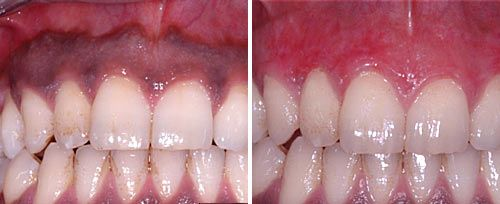

牙周炎治疗

牙周炎治疗:去除病变的牙周袋内层上皮并深度杀菌;去除根面细小结石;促进凝血及组织愈合等。

口腔激光怎么治疗口腔特色诊疗——激光治疗_https://www.jmylbn.com_新闻资讯_第4张

激光辅助治疗牙周炎前后对比图